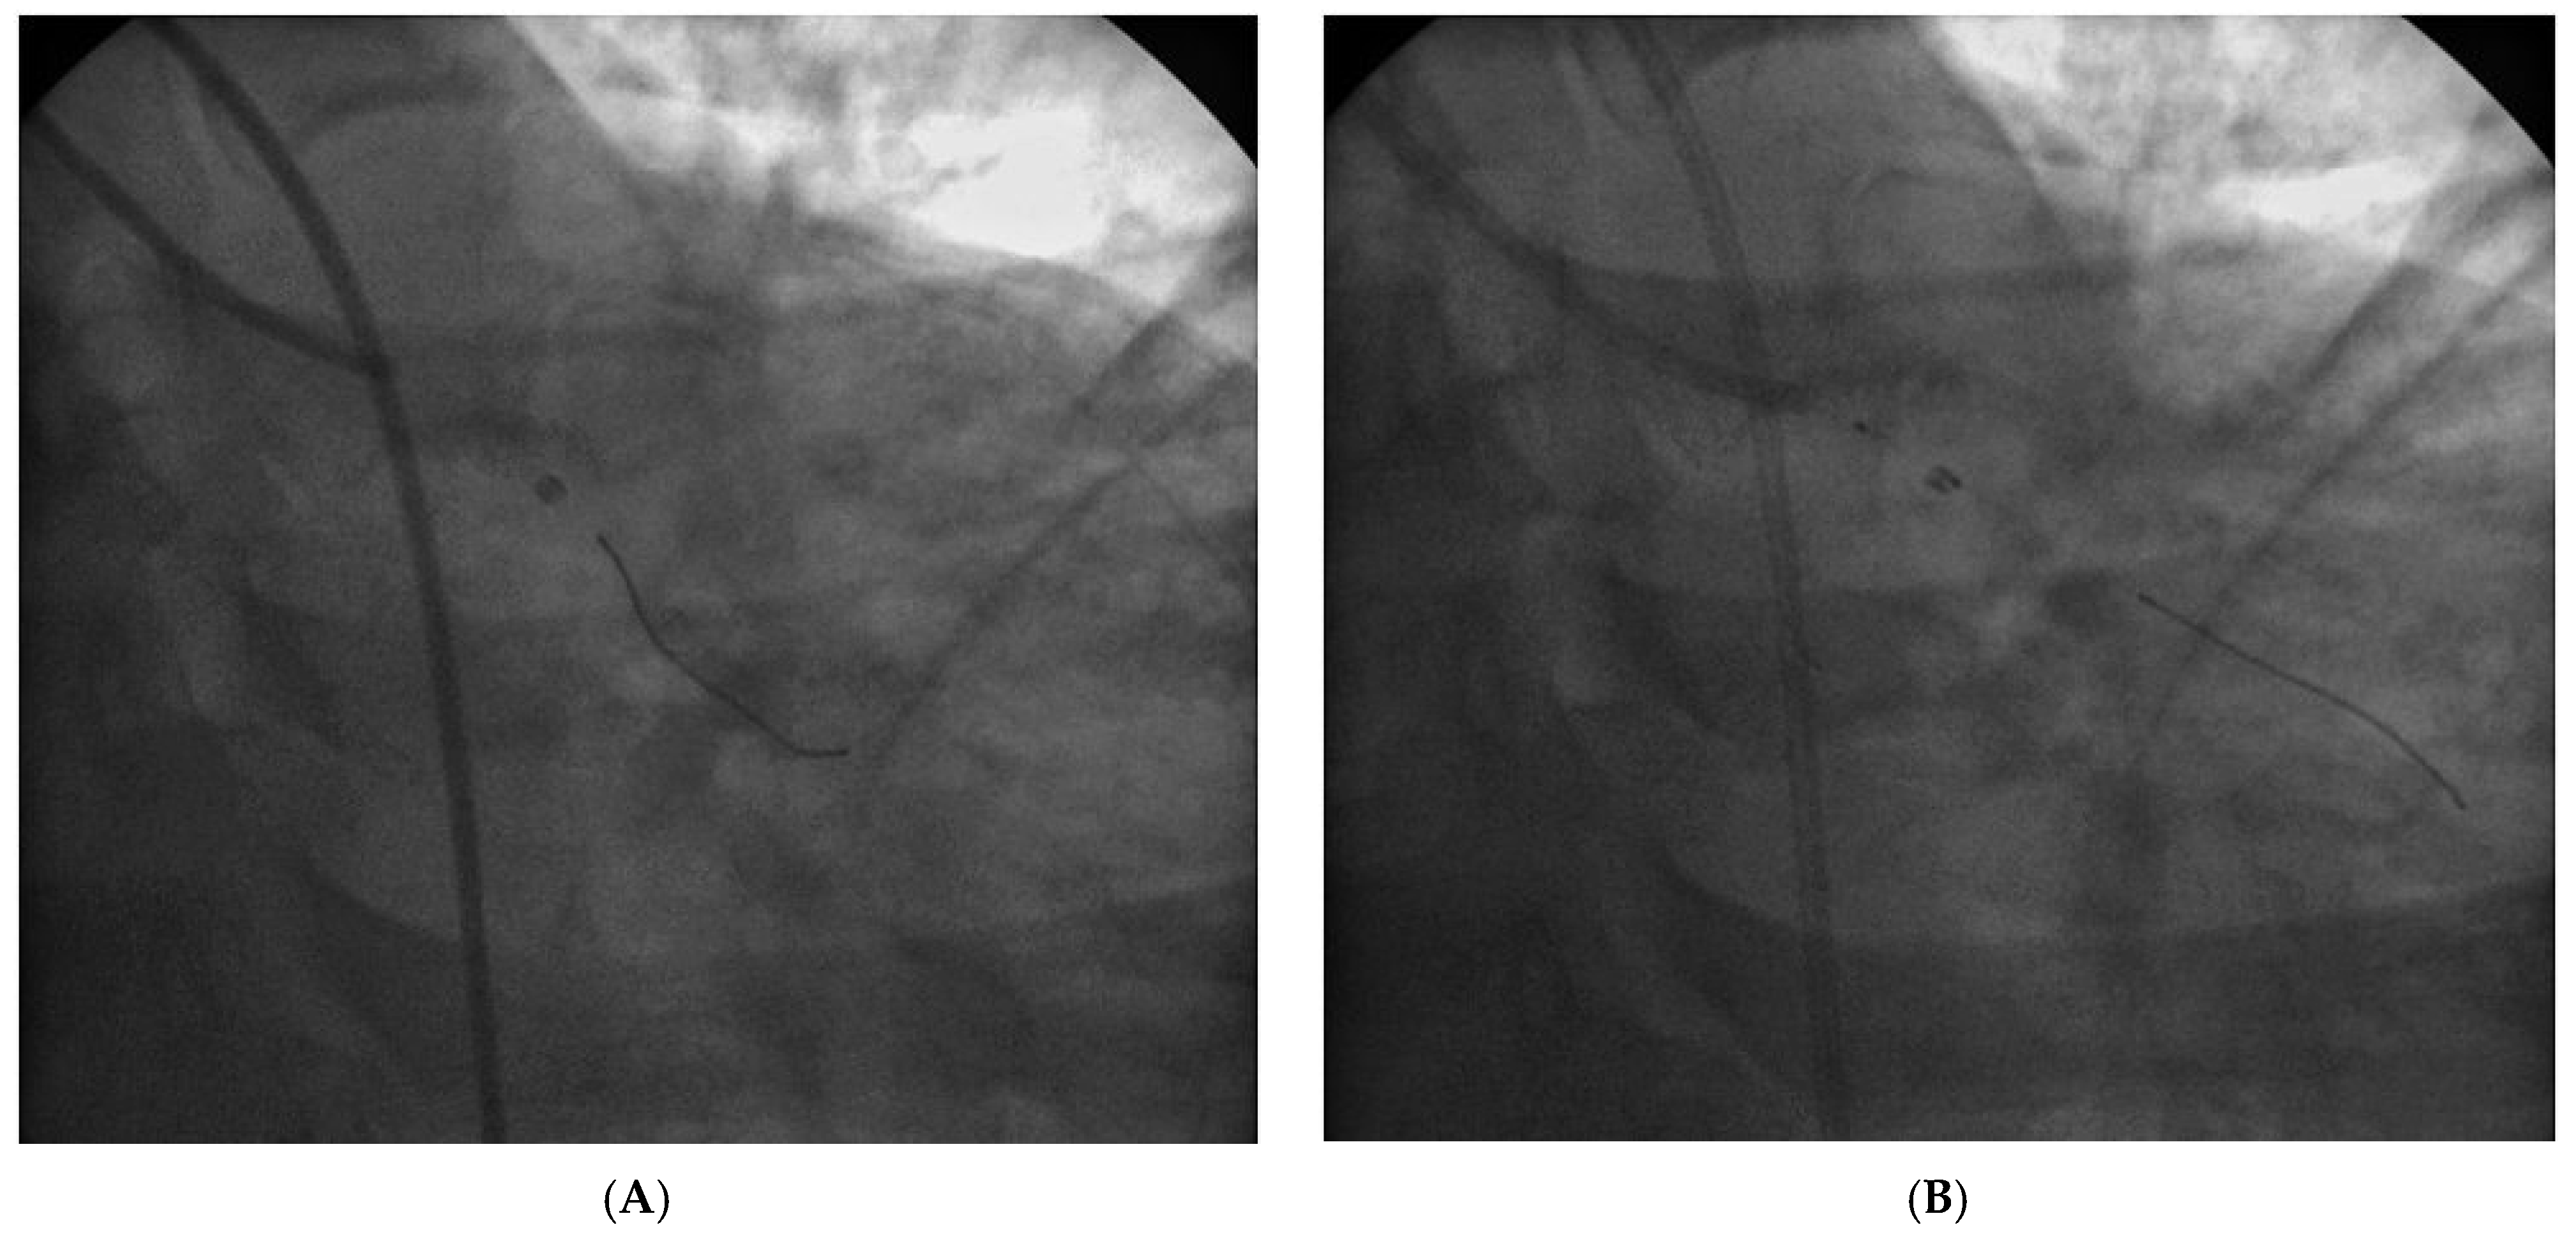

Case report